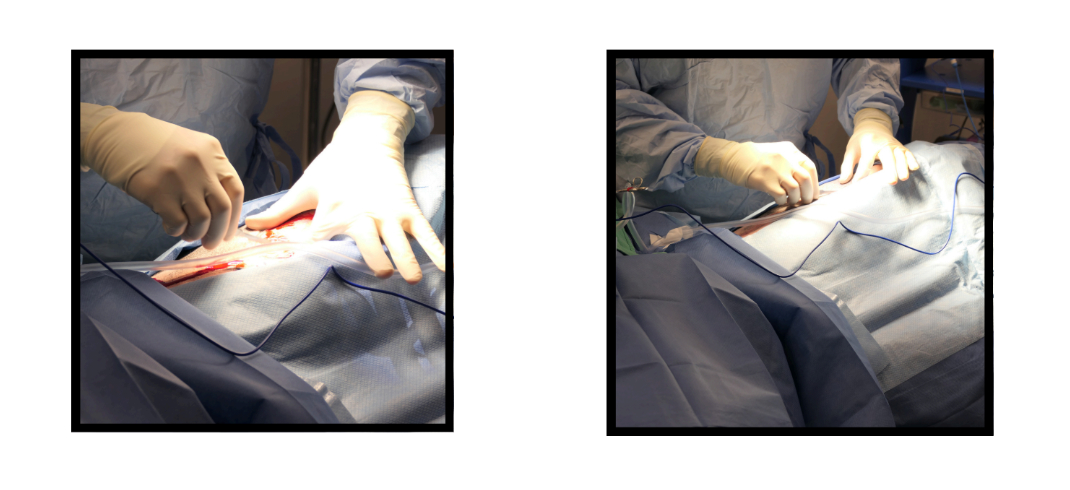

The surgery commenced with a precise ventral midline incision, extending from the xiphoid process to the caudal abdomen. This strategic approach provided optimal access to the affected organs and allowed for an efficient assessment and correction of the gastric torsion.

Upon opening the abdomen, Dr. Hillman identified the stomach in a typical GDV position, with the omentum unnaturally draped across the front. With expert care, the stomach was gently maneuvered back into its correct anatomical position. An orogastric tube was then inserted to decompress the stomach, relieving the built-up pressure and mitigating the risk of further vascular compromise.

Notably, the surgery also revealed significant damage to the spleen, marked by darkened, congested tissues indicative of hemorrhage. This necessitated a splenectomy, performed to ensure complete removal of the spleen while preserving surrounding structures.

Following the successful repositioning and stabilization of the stomach, an incisional gastropexy was executed. This procedure involved suturing the stomach wall to the abdominal wall to prevent future occurrences of torsion—a preventative measure crucial for GDV-prone breeds like Bernese Mountain Dogs.

The closure of the surgical sites was performed with equal precision, using layers of sutures that would promote optimal healing while minimizing discomfort.